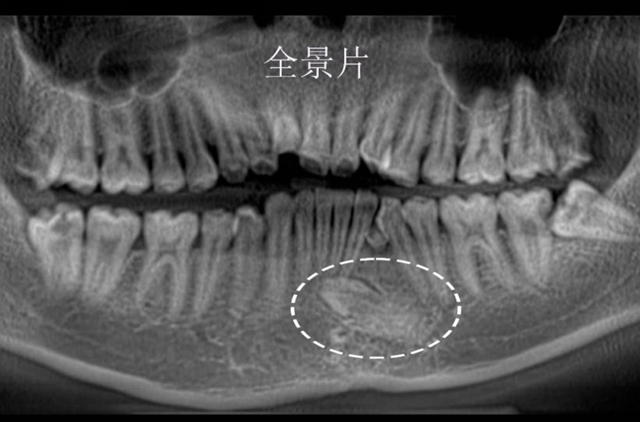

但23岁的小陈到西南医科大学附属中医医院口腔诊疗中心就诊时,却让彭培钊医生捏了一把汗——他的一颗尖牙竟“迷路”钻进了下颌骨深处,紧贴着前牙牙根,周围还缠绕着少见的粗大血管,堪称一颗潜伏的“口腔地雷”。

彭培钊发现小陈左侧下颌尖牙是颗早该脱落的乳牙,正常应该长出来的恒牙尖牙反而“躲”在了下颌骨里,牙冠直对着下前牙的牙根,只有毫厘之差。

更棘手的是,这颗埋伏牙周围还绕着一支很少见的直径0.9mm血管,比常见的颌骨内血管粗不少。

彭培钊医生解释,临床上这种“藏在骨头里的牙齿”被称为“颌骨内埋伏牙”,就像一颗“定时炸弹”,长期不干预会引发一系列问题,比如牙齿周围容易形成囊肿,压迫邻牙导致牙根吸收(严重时邻牙会松动脱落),极端情况下还可能造成颌骨病理性骨折,影响面部轮廓和咀嚼功能。

小陈的这颗埋伏牙目前已经紧邻着下前牙的牙根了,若再不处理,不仅下前牙会受牵连,后续治疗难度还会大幅增加。